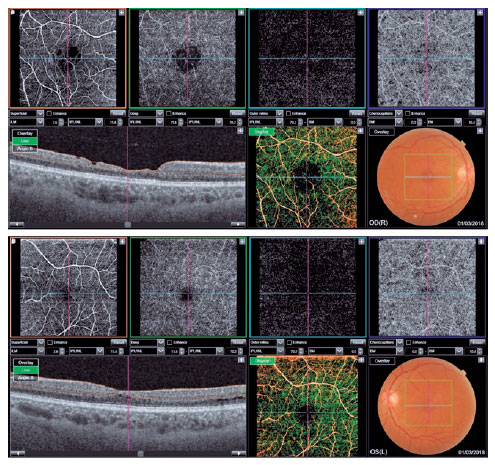

A 24-year-old man with AS confirmed by renal biopsy presented with SAH and non-dialysis-dependent CKD.

Visual acuity was 20/40 in OD and 20/30 in OS. Biomicroscopy revealed incipient lenticonus in OU. Retinal mapping showed macular pigmentary changes in OU.

On SS OCT, atrophy of the inner retinal layers was observed in OU, especially in the temporal quadrant of the macula, and defects were visible in the inner retinal layers in OD. SS OCT-A showed increased and irregular FAZ in OU (Figure 3).

02-fig03.jpg)